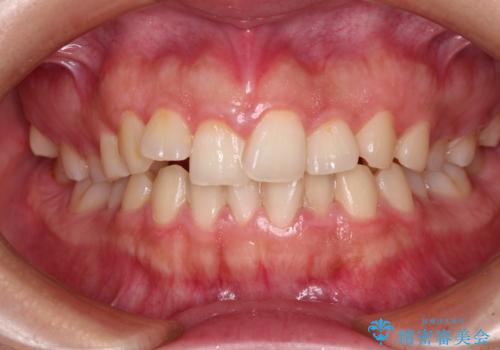

最新の症例

Latest cases